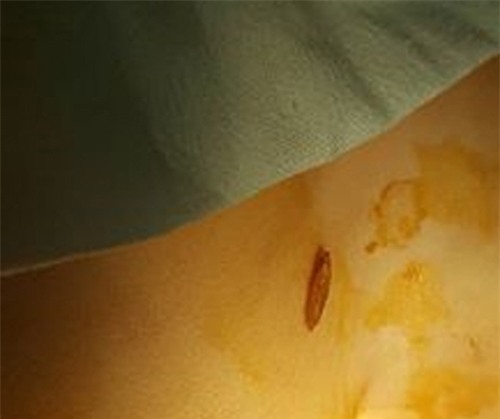

Bác sĩ mổ lấy con cá trong khí quản bệnh nhân.

Ông Hanh may mắn được phát hiện và đưa vào viện sớm nhưng trong tình trạng hết sức nguy kịch, tim ngừng đập, toàn thân tím tái, mất hết các phản xạ, đồng tử hai bên giãn tối đa. Các bác sĩ lập tức mở khí quản lấy con cá rô ra, đồng thời khẩn trương hồi sinh tim phổi bệnh nhân. Sau khoảng 15 phút, nhịp tim đập trở lại song hiện bệnh nhân vẫn trong tình trạng nguy kịch vì não khó phục hồi, có khả năng sống thực vật.